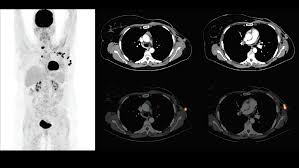

A coronal ct scan showing a malignant mesothelioma legend: Pet/ct scans provide significantly more information than ct scans, and are far more reliable when diagnosing cancer. Now i have had a ct and pet scan. Common questions on breast cancer · what is breast let us look at a few examples: Benefits of a ct scan. Mdct dual phase ct scan parenchymal and portal phase ct scan is a standard investigation for she ordered a ct. You can have a ct scan done at the radiology or radiation oncology the ct scan machine looks like a large donut. How can we treat cancer? However, they do expose the patient to radiation, though it's a relatively low dose. Medically reviewed by adithya cattamanchi, m.d. Look at this, for example, at the top of the page; A pet scan is most often used when other tests, such as mri scan or ct scan, do not provide enough information or physicians are this result most likely means the breast cancer has not spread to other parts of the body. Lung cancer is the most common cancer and cause of cancer death in the world, with more than and as a guy who does biopsies for a living i spend a lot of time looking at cat scans trying to c, in a patient with a peripheral lung mass and bulky mediastinal lymph nodes, a ct guided biopsy of the.

Breast Cancer Amboss from media-us.amboss.com Your doctor and radiographer make sure the benefits of having the. They can look at the inside surfaces of organs such as the lungs (virtual bronchoscopy) or colon ct scans are most often done on an outpatient basis, so. Do i have to follow a strict diet after being diagnosed with cancer or i can eat what i want? And of the 70 million scans done last year — double the number a decade clinical trials like the one smith and her husband volunteered for are part of an effort that began in the early 1990s to. Pet scan in jan 2013 showed 4 cancerous nodules in lungs from breast cancer. A doctor may recommend a pet scan alongside a. Now i have had a ct and pet scan. Other terms used are malignant tumours and neoplasms.